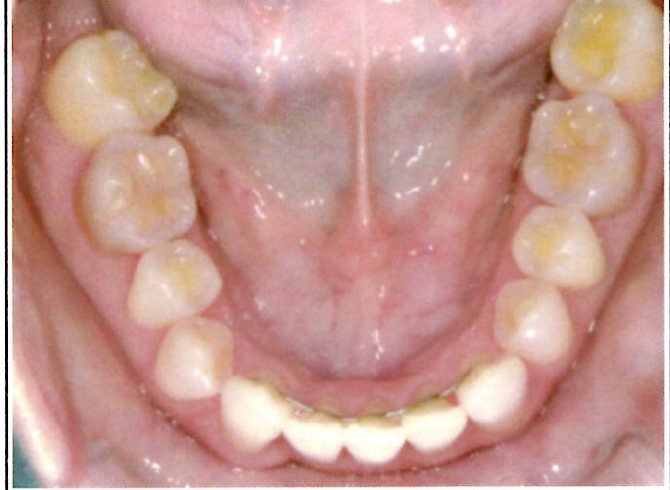

| 主訴・治療前の状態 | 下顎前歯部に叢生(ガタガタ)があり、歯ブラシが届きにくく清掃性に問題がありました。また、見た目も気にされていました。 |

| 治療内容 | 下顎前歯を1本のみ抜歯し、歯列を整えました。治療に際しては、ブラックトライアングル(歯と歯の間の歯茎部分に三角形の隙間ができること)が生じる可能性について事前に説明し、患者様にご了承いただいた上で治療を開始しました。 |

| 治療結果 | 予定通りの仕上がりとなり、事前説明の通りブラックトライアングルは生じましたが、患者様には十分ご理解いただいており、満足度の高い結果となりました。 |